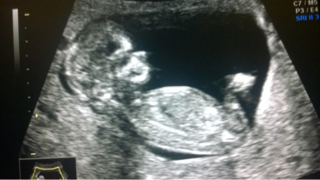

Olot on normaalit, pieni epämääräinen huono olo ajoittain vaivaa. Jollain lailla ei ymmärrä, miten siellä voi vauva kasvaa, kun ei mitään tunnu - mutta kai se voi vähäoireistakin olla. Vielä viikko ja päivä ultraan. Voi hyvän tähden!

Katjusha rv. 6+4